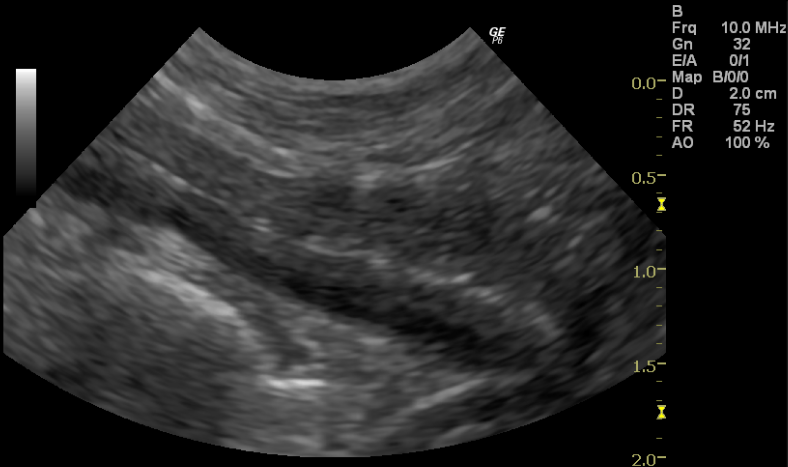

猫の消化器型高分化型リンパ腫。

高齢のねこちゃんで多い胃腸のリンパ腫。特にこの高分化型リンパ腫ではお薬の治療で長期にがんを抑えて普通の生活を送れることが多いです。

case.1

雑種猫、9歳齢、不妊雌。慢性の下痢、体重減少。組織生検にて高分化型リンパ腫の診断。

chlorambucil、predonisoneの内服治療。

症状消失、長期寛解生存。